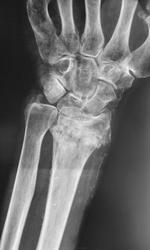

Пациент направлен на рентгенографию лучезапястного сустава, на «контроль», снят гипс.

Перелом оснований І-V пястных костей. Консолидированный перелом диафиза V пястной кости. Перелом лучевой кости в типичном месте в стадии  консолидации. Перелом головки локтевой кости с переходом на шиловидный отросток. Гетеротопическая оссификация латерального края предплечья (возможно оссификация  сухожилия). Посттравматический синостоз головчатой и крючковидной кости(?).

Думаю, что обызвествлена здесь лучевая артерия. Перелом луча не вполне типичный: оскольчатый, внутрисуставной перелом с довольно значительным смещением. Все повреждения несвежие. Посттравматического синостоза не нахожу.

определяется поднадкостничный перелом локтевой кости,остеоэпифизиолиз лучевой кости с захождением...определяется деформация(варусная????) 5-тй пястной кости..перелом основание 3-тй и 4-тй пястных костей...( есле есть ошибки пожалуйста подскажите)

Понятно , что был перелом луча в т\месте . Осложнение после ношения гипса -  поражение локтевого нерва, с остеодистрофией 4,5 пястной костей и кистей запястья.